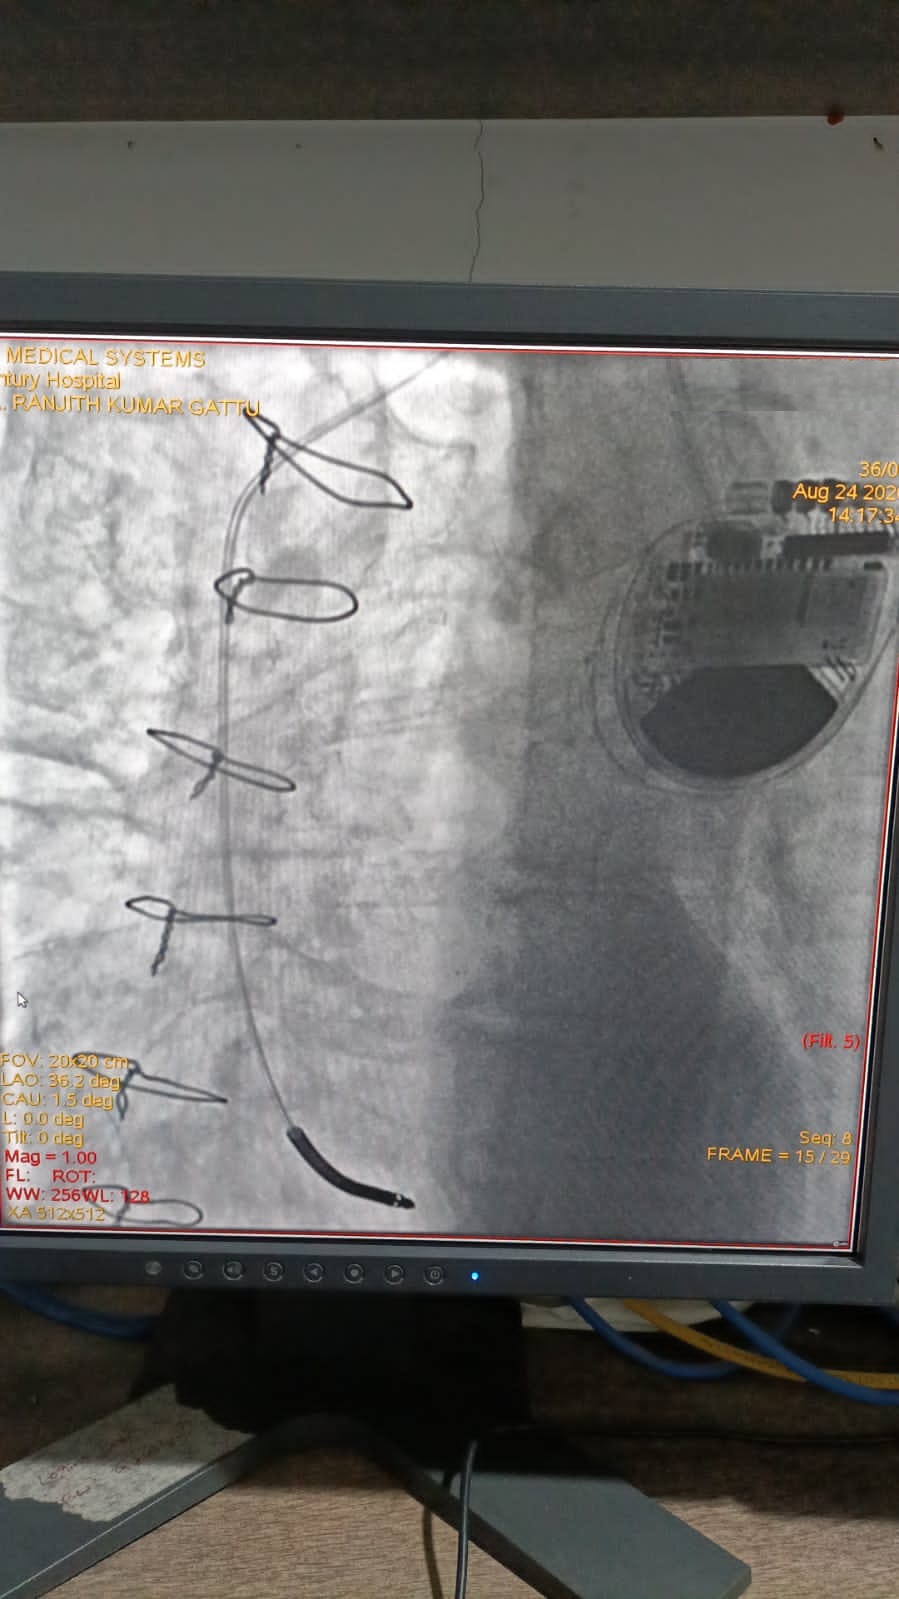

Catheter ablation of arrhythmias

Right Coronary Diseased Artery